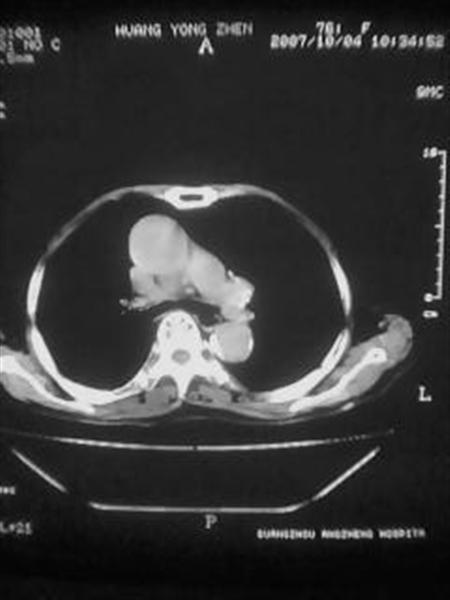

标题: CT10080:F76Y,各位老师发表高见!!! [打印本页]

标题: CT10080:F76Y,各位老师发表高见!!!

右下肺周围型肺癌伴双肺右侧叶间 胸膜及右肺门淋巴结转移

考虑:肺癌伴肺、胸膜 纵隔淋巴结转移可能性大!